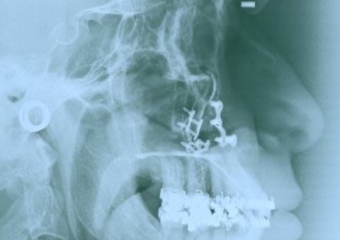

Telerradiografia inicial

Telerradiografia final